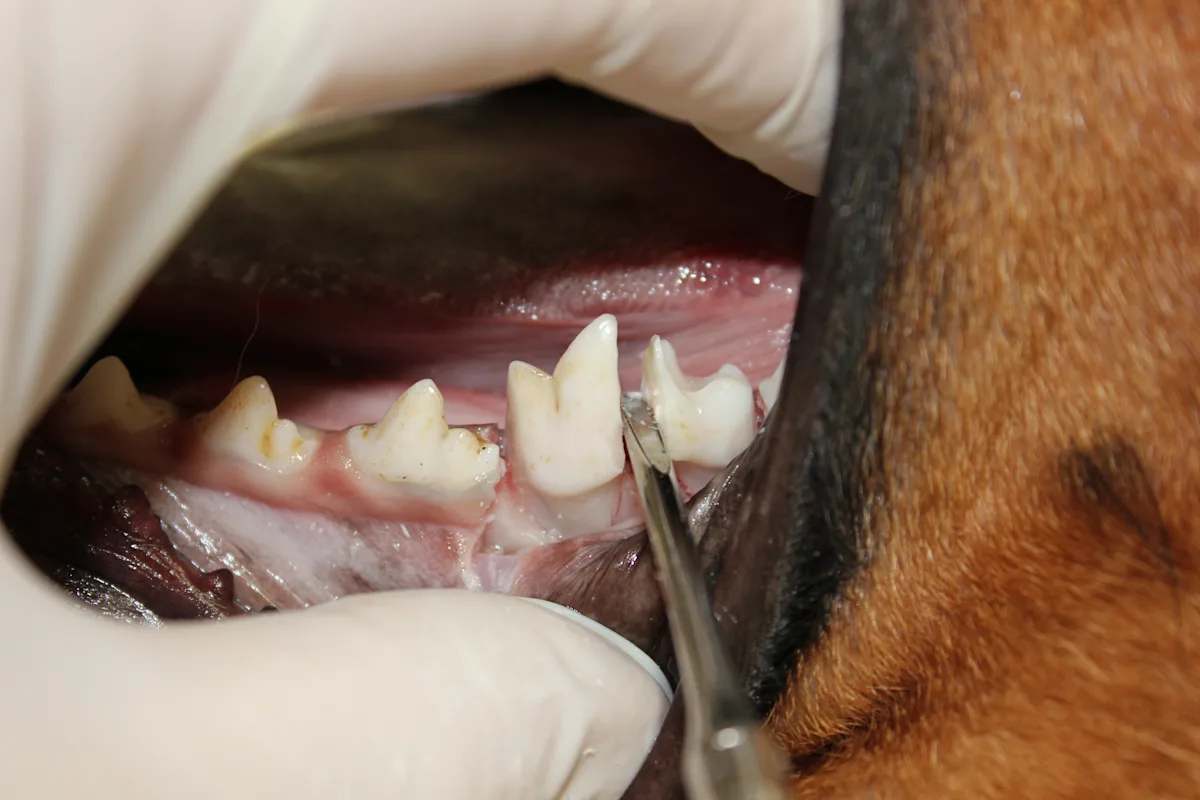

Find the periodontal ligament space and elevate the mesial root (larger of the 2 roots) followed by the distal root. (A) Place a finger stop on the tip of the presharpened elevator/luxator and gently slide it into the periodontal ligament space. Rotate the elevator/ luxator until resistance is met, hold for 15 seconds, then repeat by rotating in the opposite direction. Move the elevator/luxator around the ligament space and repeat until completely around the tooth segment. (B) When the tooth segment becomes mobile, use the extraction forceps to rotate the segment until resistance is met, hold for 15 seconds, then repeat in the opposite direction. Position the jaws of the extraction forceps parallel to the axis of the tooth root. Once the mesial root has been extracted, repeat the procedure for the distal root.